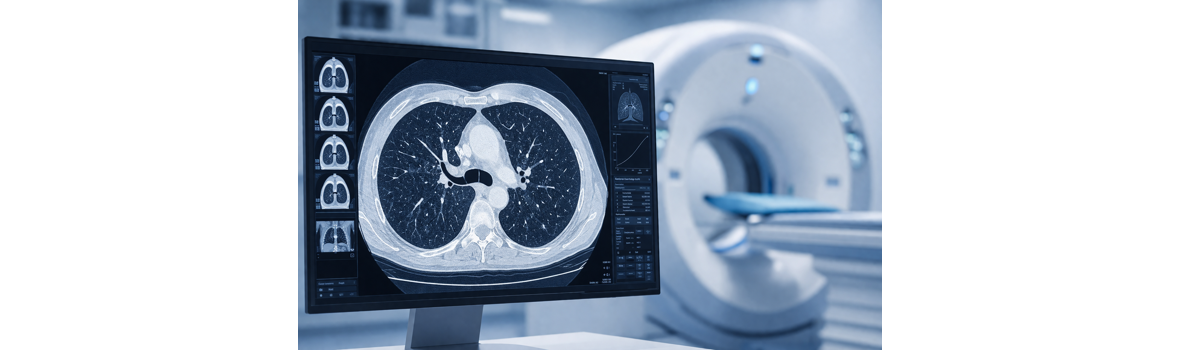

In unserer Praxis bieten wir zur Früherkennung von Lungengewebeveränderungen und Tumoren hochauflösende Niedrig-Dosis-HRCT-Untersuchungen der Lunge nach ICOERD-Richtlinien an, bei der die effektive Strahlendosis bei nur etwa 1mSv liegt. Zur Beurteilung des Lungengewebes kann bei einer HRCT-Thorax-Untersuchung auf die zusätzliche Gabe von Kontrastmittel verzichtet werden.